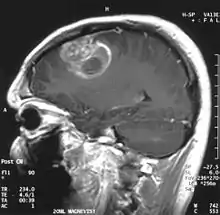

.jpg.webp)

When viewed with MRI, glioblastomas often appear as ring-enhancing lesions. The appearance is not specific, however, as other lesions such as abscess, metastasis, tumefactive multiple sclerosis, and other entities may have a similar appearance.[42] Definitive diagnosis of a suspected GBM on CT or MRI requires a stereotactic biopsy or a craniotomy with tumor resection and pathologic confirmation. Because the tumor grade is based upon the most malignant portion of the tumor, biopsy or subtotal tumor resection can result in undergrading of the lesion. Imaging of tumor blood flow using perfusion MRI and measuring tumor metabolite concentration with MR spectroscopy may add diagnostic value to standard MRI in select cases by showing increased relative cerebral blood volume and increased choline peak, respectively, but pathology remains the gold standard for diagnosis and molecular characterization.